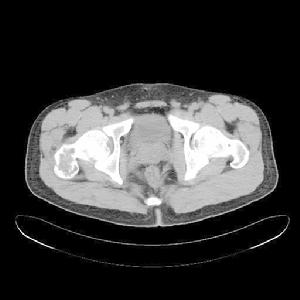

有經驗的骨腫瘤醫生僅憑X線平片就可以作出骨囊腫的臨床診斷。病變灶為邊界清晰的液性低密度灶,四壁為薄層的硬化灶殼。病變灶略向近骨骺的乾骺部位擴大。病灶非偏心性,也不破壞骨外殼,更不會突破骨質形成骨膜外反應骨,除非是在病理骨折後的癒合期。有時脫落的骨皮質成份落入囊腔中,X片顯示被稱為“落葉征”(FallenleaforFallenfragment)。當病灶發生在骨盆,CT掃描對病灶部位及囊腫形態的判斷有價值。MRI可以明確囊內富含的液性成分。骨ECT掃描表現為外周薄的濃集而中央病灶冷區。

二CT:

1.骨囊腫一般多呈圓形、卵圓形低密度骨質缺損,邊緣清晰,無硬化。

2.局部骨皮質變薄呈囊性膨脹。

3.少數囊腫內可見骨性間隔,呈多房改變。

4.骨囊腫內的CT值多為水樣密度,有出血時密度可升高。

5.增強掃描囊腫不強化。